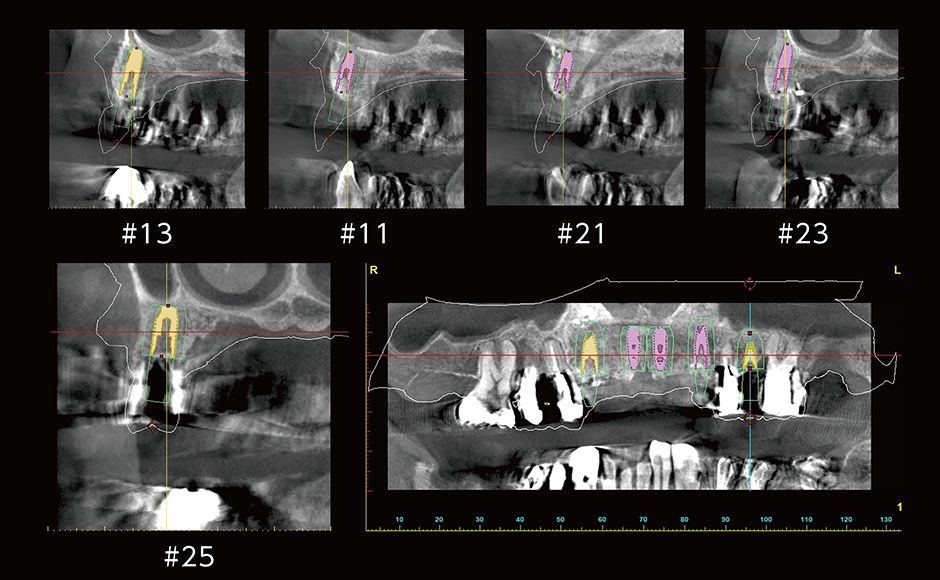

症例2:#13〜#25インプラントブリッジ